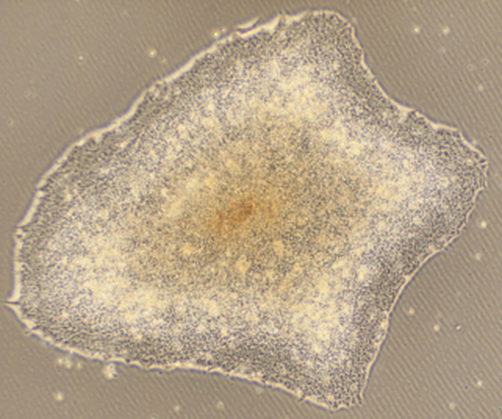

画像

図 ヒト毛包由来培養細胞から再構築した毛包類似構造(研究内容はFukuyama et al. Front Cell Dev Biol 2021に掲載)